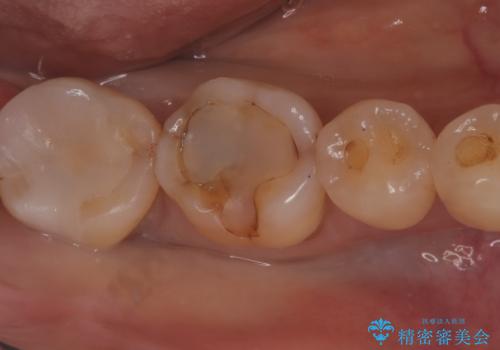

今回残存歯質量から破折のリスクを説明し、クラウンでのやり替えも提案しましたが歯質切削量が多くなることから一度インレーで様子を見ることとなりました。

セラミックインレーセット時はラバーダム防湿を行っています。